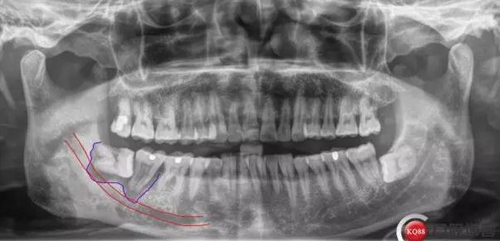

X線及CBCT檢查:47、48根尖周區(qū)大面積低密度影像,波及下牙槽神經(jīng)管,部分區(qū)域至神經(jīng)管以下。CBCT顯示神經(jīng)管走形于47根尖炎癥區(qū)下方(已侵犯)48炎癥區(qū)頰側(cè)(已侵犯)

術(shù)前CBCT分析

對于曲面斷層片的分析,當(dāng)智齒埋伏牙的根尖與下牙槽神經(jīng)有重疊影像時(shí),常常可采用觀察重疊部分牙根的牙周膜和硬骨板是否連續(xù),下頜管是否比牙根密度高,下頜管是否變窄等,來辨別牙根與神經(jīng)管的位置關(guān)系。當(dāng)然曲面斷層片也很難避免其失真變形的自身局限性。拍攝CBCT能更為直觀預(yù)估其風(fēng)險(xiǎn)。但切記盲目的嘗試和挑戰(zhàn)。